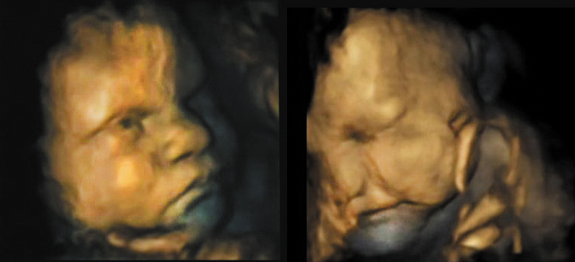

"Facial Expressions Develop in the Womb" Life Science

Life Science // by Wynne Parry, LiveScience Senior Writer // Photo credit Nadja Reissland // 07 September 2011

Before he or she is born, a fetus begins to move his or her face — parting lips, wrinkling a nose or lowering a brow for example — making movements that, when combined, will one day assemble expressions we all recognize in one another. A new study has shown that, as the fetus develops, these facial motions become increasingly complex.

While it was known that fetuses could form expressions while in the womb, this study tracked facial movements over time. "What we have found for the first time is you can look at the progression of the complexity of the movements," said lead study researcher Nadja Reissland, a senior lecturer at the University of Durham in the United Kingdom.

By capturing images of two fetuses periodically from 24 to about 35 weeks of gestation, the researchers watched individual, unrelated movements progress to complex combinations, associated with recognizable facial expressions. In addition to tracking 19 total facial movements, the study focused on sets of movements associated with two expressions, one associated with crying, the other laughing. Over time, the movements associated with these began to appear in more complex combinations. They used 4-D ultrasound images, which resemble video, to track the facial motions of twofemale fetuses.

At 24 weeks, fetuses were more likely to make a single movement, like a widening of the lips for example, all by itself. Then, as the weeks passed, they began combining the movements, putting, say, a lip widening movement with a nose wrinkle. By about 35 weeks, combinations of three and four movements associated with the two expressions had surpassed single or double movements. A similar trend occurred when the researchers looked at all 19 movements.

Reissland pointed out that these facial movements don't mean the fetuses were experiencing emotion. We can see the expressions which we can recognize; we can't say whether the fetus has emotion," she said. "They [don't] have yet the cognition necessary to have the emotions."

Rather, these motions are likely a form of practice, as the fetuses prepare to enter the social world, where they must form bonds with others. Fetuses also suck their thumbs in the womb and make breathing motions, both precursors for important activities once they are born, she said.

For future research, Reissland is interested in looking for other fetal facial expressions associated with anger, smiling and sadness. This study appeared Aug. 31 in the journal PLoS ONE.